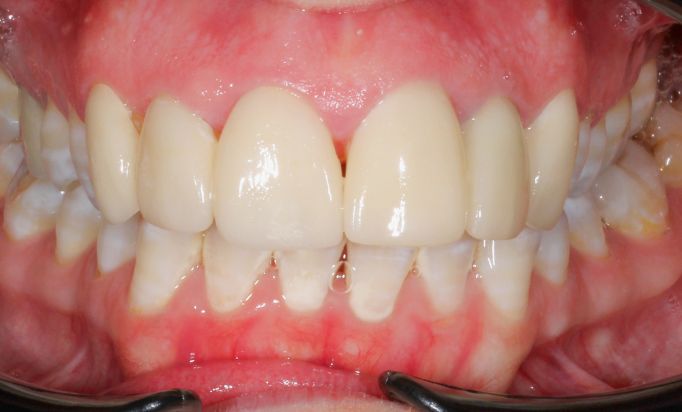

INVISALIGN®

Invisible treatment, visible results

Achieve stunning teeth alignment without the metal brackets.

Aligned teeth, confident smiles